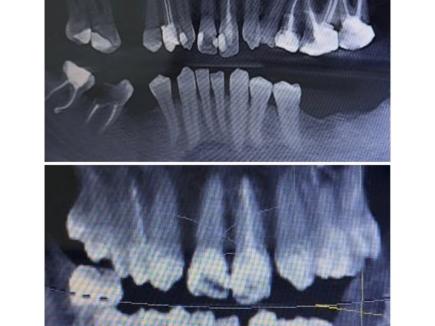

В данном клиническом случае мы показываем как можно эстетически подкорректировать врожденные аномалии. У пациента с рождения отсутствуют вторые резцы, их место заняли клыки.

Визуально мы видим несоответствие формы,  наличие промежуткав между зубами, а также дисколорит.

Было предложено исправить данный дефект с помощью коронок из диоксида циркония.